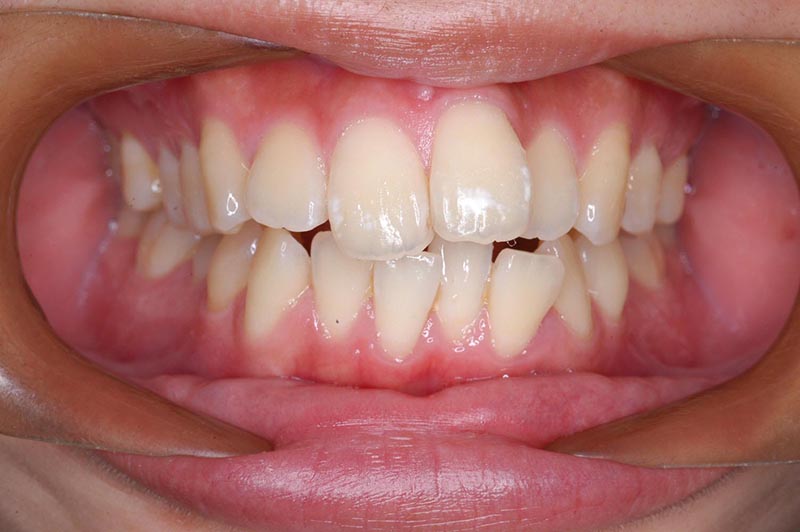

初診時

主訴 口が閉じづらい 診断名 アングルⅠ級上下顎前突症例

初診時年齢 19歳5ヵ月 性別 動的治療期間 26ヵ月

口腔内所見 大臼歯関係はⅠ級。顔面正中に対して上顎正中は一致しており、下顎正中は右側に偏位していた。上下顎前歯は大きく唇側傾斜し、overjetが7.8mmの上突咬合、両突歯列、叢生歯列弓であった。